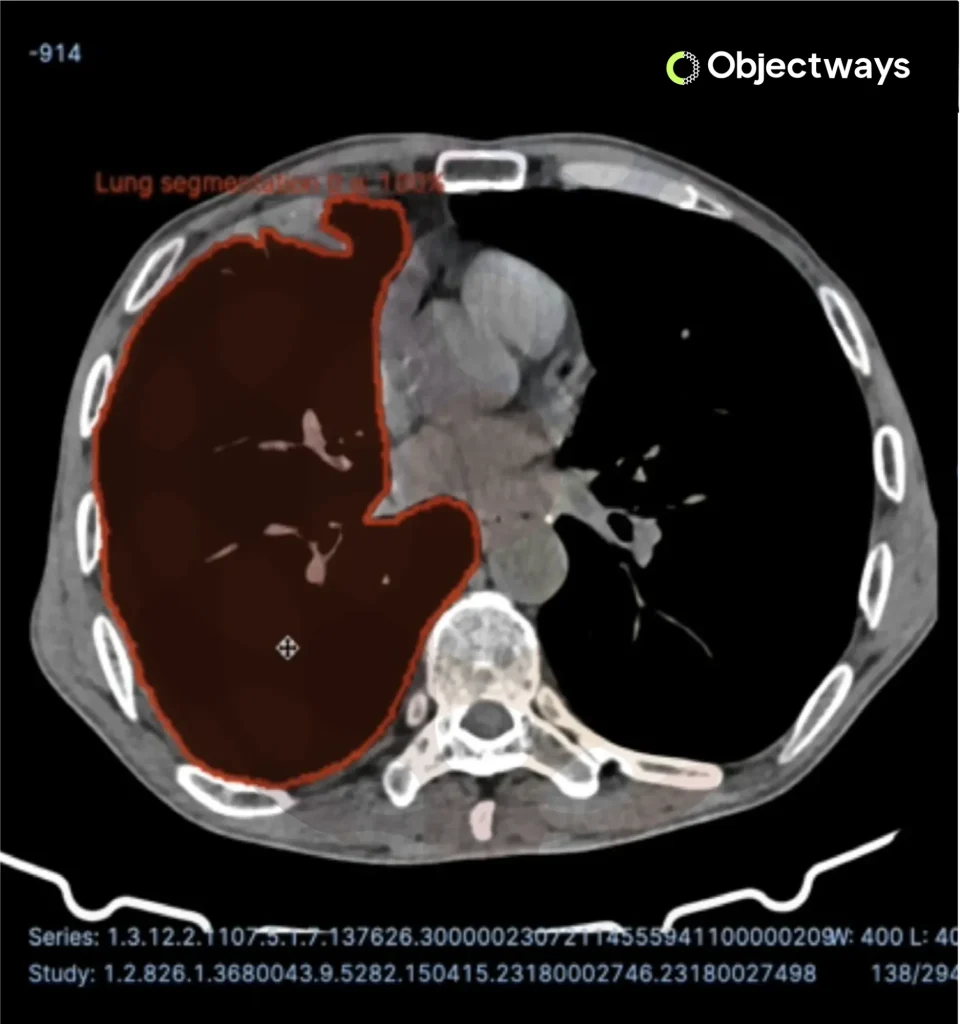

Using Computer Vision to Detect Brain Tumors